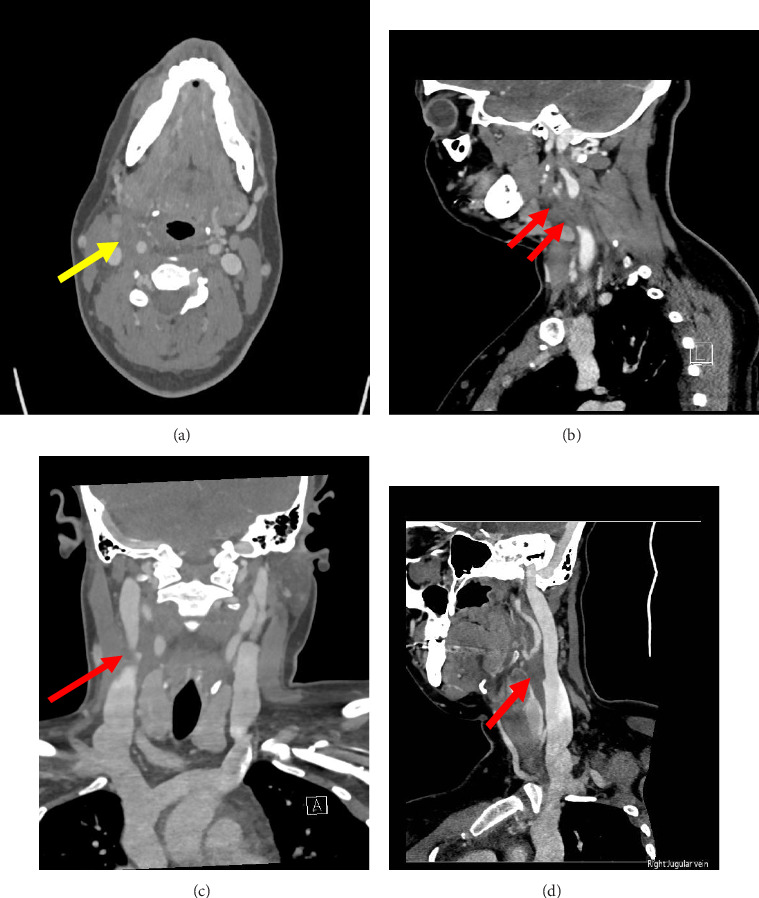

背景:Lemierre综合征是一种罕见但潜在致命的感染,通常继发于细菌性咽部感染。它的典型特征是菌血症,最常见的是由于坏死性梭杆菌和颈内静脉血栓性静脉炎。如果不及时治疗,可能会导致脓毒性栓塞,潜在地损害肺、肝、脑或其他器官。本报告描述了一名患有链球菌性咽炎的年轻女性的Lemierre综合征变体,她发展为核梭杆菌菌血症和孤立的面部静脉血栓性静脉炎,强调了早期诊断和治疗的重要性。病例介绍:33岁女性,无明显既往病史,表现为喉咙痛、寒战、右侧面部和颈部疼痛。她最初在一家急诊诊所被诊断为链球菌性咽炎,后来由于出现严重僵硬和发烧,她很快被送到急诊科。血液培养显示有核梭杆菌生长,尽管颈部软组织初步成像呈阴性,但面部和颈部疼痛恶化,这引起了对lemerre综合征的怀疑。随后的CT静脉造影证实了右侧面部静脉的孤立血栓形成。患者给予甲硝唑治疗4周,头孢曲松治疗2周,出院时病情稳定。结论:本病例强调了对细菌性咽炎患者保持对Lemierre综合征的怀疑的重要性,特别是当出现面部疼痛等非典型症状时。虽然颈内静脉最常受影响,但也可能发生面部静脉血栓形成。早期抗生素治疗对于预防脓毒性休克和栓塞等严重并发症至关重要。

Background: Lemierre's syndrome is an uncommon yet potentially fatal infection, classically secondary to bacterial pharyngeal infections. It is typically characterized by bacteremia, most frequently due to Fusobacterium necrophorum and internal jugular vein thrombophlebitis. If untreated, septic embolization may result, potentially damaging the lungs, liver, brain, or other organs. This report describes a variant of Lemierre's syndrome in a young woman with streptococcal pharyngitis, who developed Fusobacterium nucleatum bacteremia and isolated facial vein thrombophlebitis, highlighting the importance of early diagnosis and treatment. Case Presentation: A 33-year-old woman with no significant past medical history presented with sore throat, chills, and right-sided facial and neck pain. Initially diagnosed with streptococcal pharyngitis at an urgent care clinic, she presented to the emergency department soon afterwards due to the development of severe rigors and fever. Blood cultures revealed growth of Fusobacterium nucleatum, raising suspicion for Lemierre's syndrome in the setting of worsening facial and neck pain despite negative initial imaging of the soft tissue of the neck. A subsequent CT venogram confirmed isolated thrombosis of the right facial vein. The patient was treated and discharged in stable condition on a 4 week course of metronidazole and 2 weeks of ceftriaxone. Conclusion: This case emphasizes the importance of maintaining suspicion for Lemierre's syndrome in patients with bacterial pharyngitis, especially when atypical symptoms such as facial pain occur. Although the internal jugular vein is most commonly affected, facial vein thrombosis may also occur. Early antibiotic treatment is critical for preventing severe complications including septic shock and embolization.